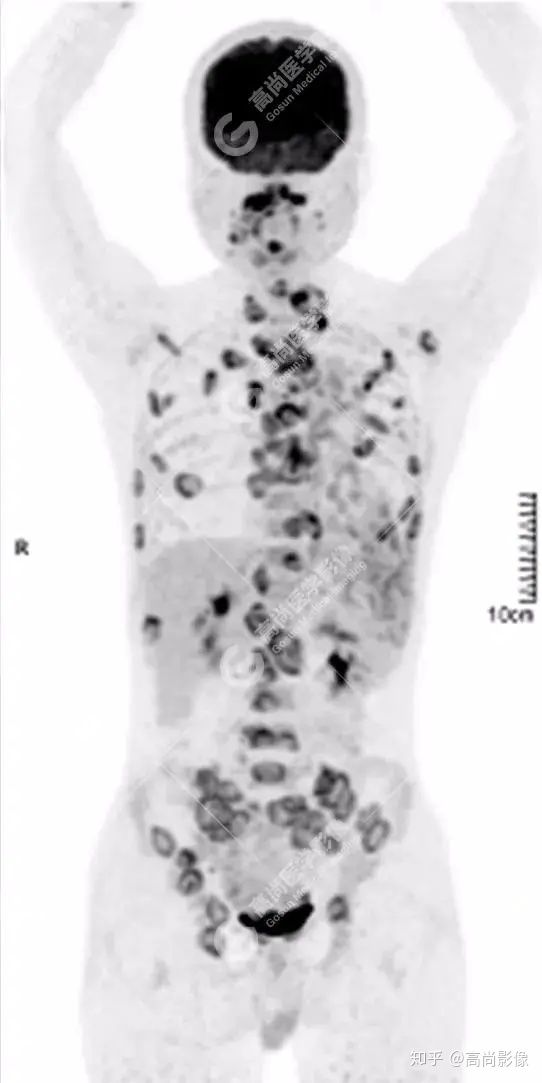

全身多處骨質(zhì)破壞,代謝不均性增高

全身多發(fā)高代謝腫大淋巴結(jié),中央代謝缺損